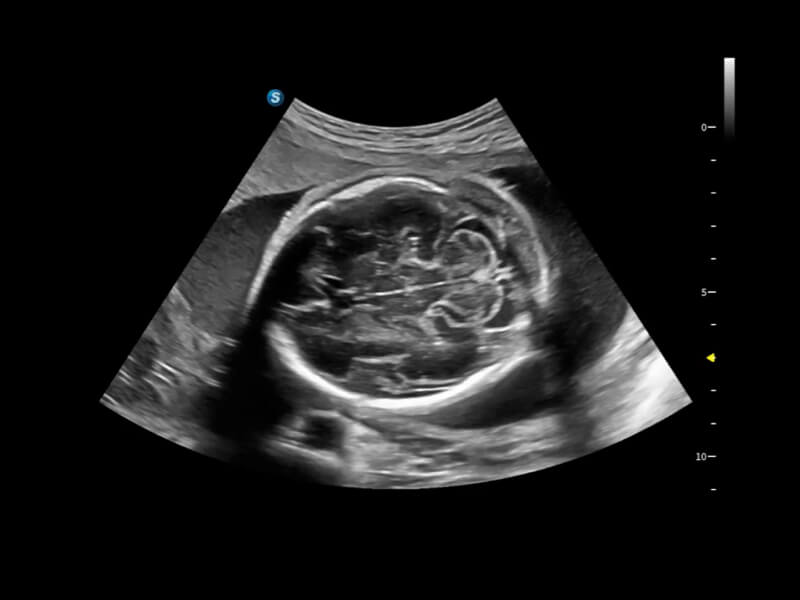

Diese neuen Perspektiven ermöglichen die Betrachtung der Anatomie aus Volumenperspektiven, mit fortschrittlicher Bewertung und intelligenten Scan-Tools. Sie bieten Klinikern mehr Informationen und helfen, Anomalien früher als je zuvor zu identifizieren.

• S-Live Studio liefert eine brillante, realistische Hautvisualisierung in Echtzeit, indem es die Lichtausbreitung auf der Hautoberfläche simuliert und so die Tiefe und Authentizität des dreidimensionalen Bildes bereichert.

• One-Stop-Lösung zur automatischen Standard-Flugzeugerfassung und -messung. Mit nur einem Klick werden 29 Standardabschnitte von fetalen Ultraschallbildern intelligent identifiziert, und 13 biometrische Messungen werden automatisch mit hoher Intelligenz, Genauigkeit und Effizienz erfasst, um eine beispiellose Leichtigkeit während des Betriebs zu ermöglichen.